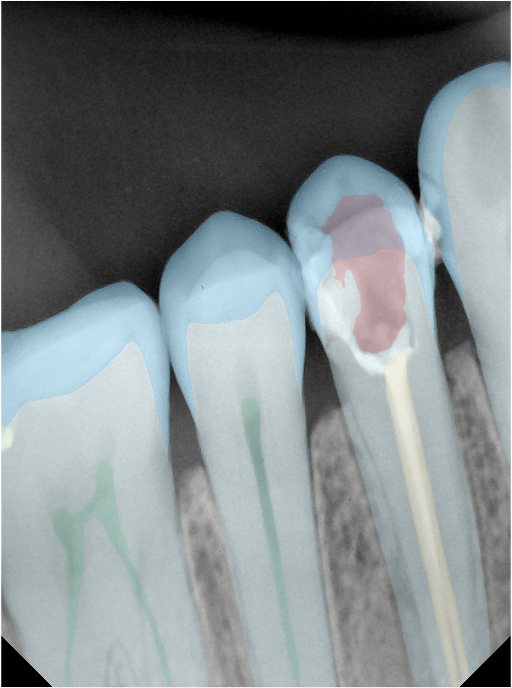

CR/DR 牙齿分割阶段记录

当前进展

- 完成了 CR/DR 牙齿相关分割训练

- 当前结果已经达到阶段预期,但仍有细节问题需要继续处理

相关测试

遇到的问题

- 训练过程中出现过 mask 下移问题

- 部分结果会出现 box 填充异常

- mask 边缘仍然有比较明显的锯齿感

参考

第二版算法问题测试

Updated: 2026-04-13(更新日期)

| 第一版 | 第二版 | 是否解决 | |

|---|---|---|---|

![]() | ![]() ![]() 边角识别有问题 龋齿识别不全 牙髓识别不全 | ![]() | 解决 |

![]() | ![]() 边角识别有问题 识别信息有误 自查(牙冠识别不全) | ![]() | 解决 |

![]() | ![]() ![]() 边角识别有误 大范围填充识别遗漏 | ![]() | 解决 |

![]() | ![]() 识别信息不全 | ![]() | 解决 |

![]() | ![]() ![]() 边角问题 牙胶识别不全 牙冠识别不全 | ![]() | 解决 |

![]() 换图片 | ![]() | ![]() 牙冠部分稍微白了一些就识别成小范围修补,部分判断异常 | 部分解决,修复类略敏感,牙冠部分稍微白了一些就识别成小范围修补,部分判断异常。 |

![]() | ![]() ![]() 牙冠识别不全 牙髓不全 根尖炎龋齿识别有误 | ![]() | 解决 |

![]() | ![]() | ![]() | 解决 |

![]() 换图片 | ![]() | ![]() | 解决 |

![]() | ![]() 牙冠识别有误 | ![]() | 解决 |

![]() 换图片 | ![]() ![]() 边角识别有误 | ![]() 修复类敏感 | 部分解决,图像过白,导致修复类判断异常。 |

![]() 换图片 | ![]() 牙冠识别不全 | ![]() 修复类敏感 | 部分解决,图像过白,导致修复类判断异常 |

结论:修复类出现了不鲁棒的情况,后续需要加入轮廓的扩充数据进行增强。